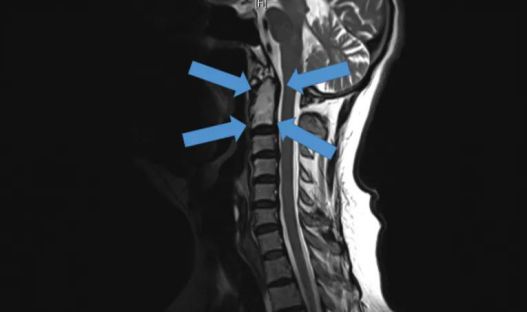

△2015年底,世界首例采用3D打印椎骨植入物

脊柱行業也是未來醫療器械市場,最新發展趨勢之一。通過3D打印技術,來達到創新產品的目的,該技術可以促進骨骼向內生長,并改善植入物對脊柱骨的固定,縮短制造流程,提高患者滿意度,從而在某些情況下更具成本效益。

例如,Medtronic鈦金屬3D打印平臺——TiONIC技術。使用激光方法制造具有增強表面紋理的植入物。Artic-L是該公司使用TiONIC技術制造的第一款金屬植入物。可供外科醫生在脊柱手術中使用。還有K2M的Lamellar,同樣采用鈦制造3D脊柱植入物。使用金屬3D打印技術特有的優勢之一,可實現曾經被傳統制造技術,認為不切實際的結構。